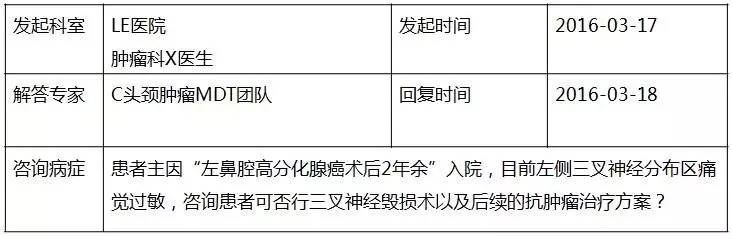

【MDT病例分享】鼻腔腺癌术后1例

患者:男性,58岁,主因“左鼻腔高分化腺癌术后2年余”入院。

咨询目的:

1.患者疼痛原因考虑肿瘤脑神经侵犯或放射性损伤?

2.目前患者药物止痛效果差,可否行放疗、手术、介入手段行神经毁损?

3.后续的抗肿瘤治疗方案。

基础信息

▼患者病情描述